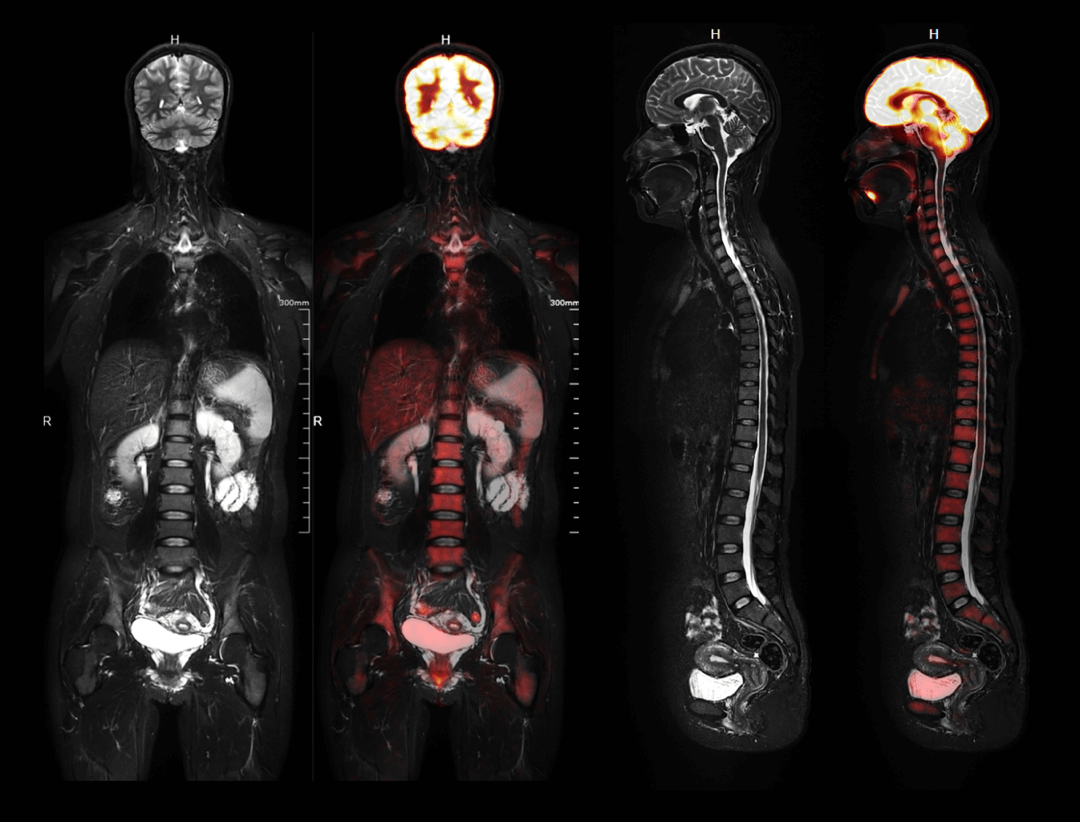

Imagistică whole-body

Scanare whole-body în trei poziții de pat, cu vizualizare completă a organelor într-o singură poziționare.

uPMR 790 permite imagistică simultană PET/MRI cu rezoluție temporală și spațială ridicată. Această tehnologie redefinește standardele clinice și de cercetare, oferind imagini anatomice și funcționale în timp real.